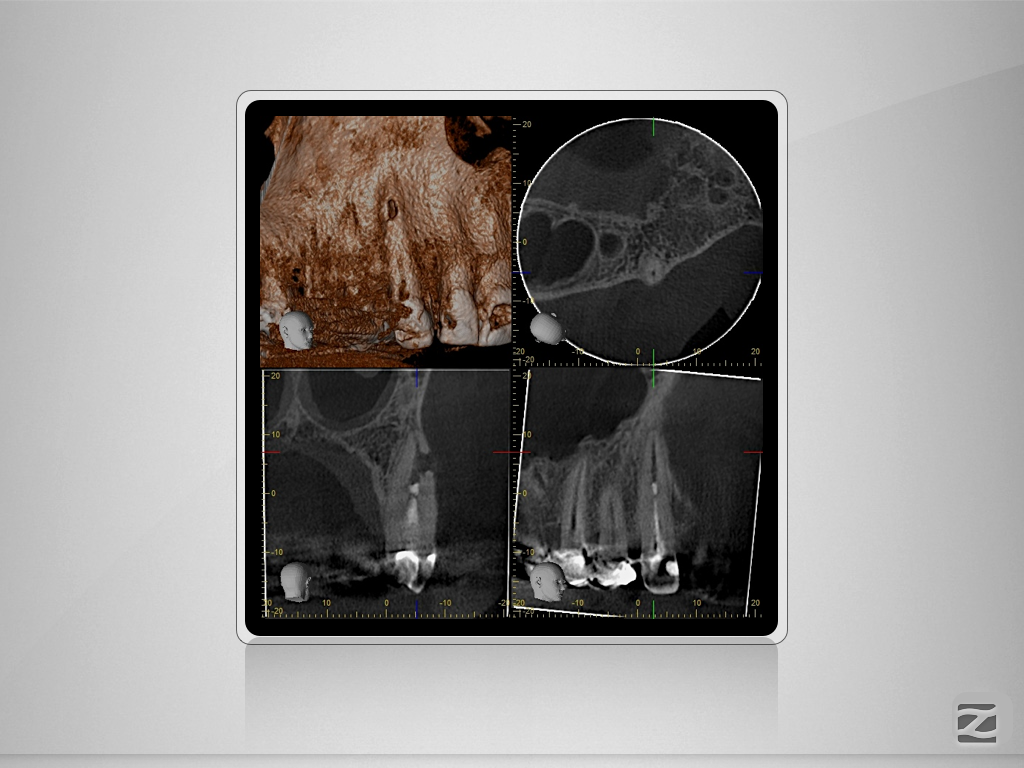

2D vs. 3D (XXVIII) – der Fallbericht